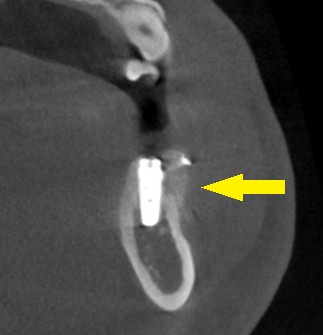

人工骨を使用しての骨造成術を併用して、インプラント埋入を行なうことで了承されましたので、本日、同手術を施行しました。

下の写真に手術前後のCTを示します。